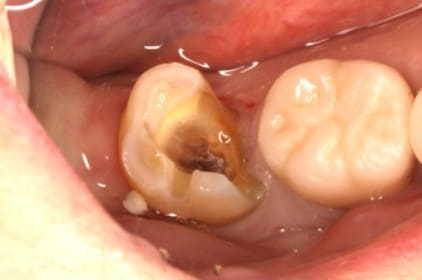

昔から噛んだ時に違和感があった。「噛み合わせが強いことが原因だろう」と言われ、削って噛み合わせの調整を何年も受けていた。詰め物が取れたことをきっかけに調べて来院。

歯の中を触ると膿がかなりでてきました。

根管の中が無菌に近い状態になるように洗浄を繰り返します。

根管の中を封鎖し、根管治療終了

根管治療が終わったところが、また隙間から感染しないように、

上から被せを精密に接着させ、密封。

治療後病気がなくなり骨が再生した